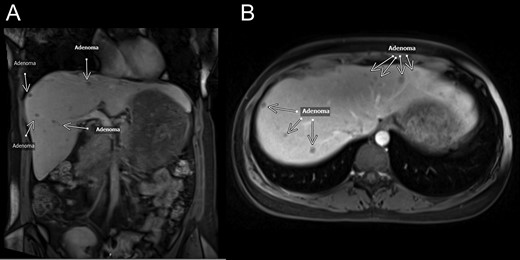

The patient is a 41-year-old female with a past medical history of a living-unrelated renal transplant for end-stage renal disease due to focal glomerulosclerosis. During evaluation for pyelonephritis, a CT scan found multiple non- cystic liver lesions in both lobes. Her medications were significant for maintenance immunosuppression, consisting of tacrolimus 1 mg, cellcept 500 mg, prednisone 5 mg. She denied any history of hepatitis, OCP use or diabetes. Her BMI was 26. She was referred to the hepatobiliary clinic where her initial work-up consisted of lab work, colonoscopy, ultrasound and MRI. Her AFP and CEA were normal at 2.3 and 0.8, respectively. Her colonoscopy was normal. An ultrasound revealed multiple echogenic round lesions in both lobes with no ductal dilatation. An MRI showed ~50 hyper-intense lesions measuring up to 1 cm in both right and left lobes (Fig. 1). A percutaneous liver biopsy was found to be normal hepatic parenchyma. She was managed expectantly for a year until a follow-up MRI showed an increase in size and number of her liver lesions, some of which contained a fatty component.

MRI—coronal (A) and transverse (B) MRI sections showing multiple lesions within both lobes of the liver. White arrows mark lesion locations. Per radiology notes, each lesion measured from 0.5 to 1.5 cm in diameter. There were at least 50 lesions in total.